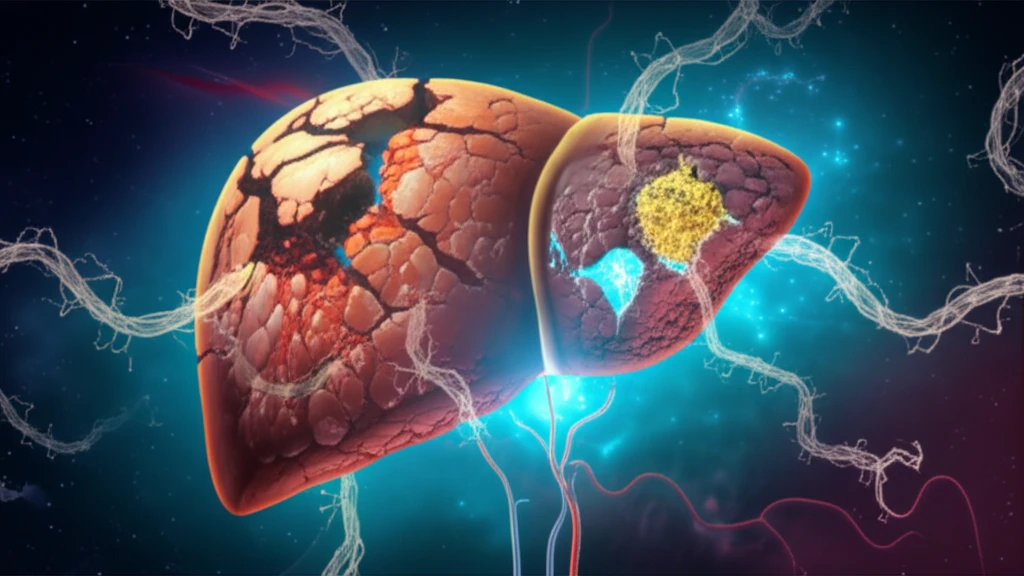

The liver, with its incredible ability to regenerate, faces significant challenges when chronic disease or major surgery come into play. Liver ischemia-reperfusion injury (IRI) and regeneration deficiency are major hurdles for patients undergoing liver surgery, especially those with pre-existing liver conditions. Imagine needing a liver transplant, but your liver just isn't strong enough to bounce back. This is where the innovative research into Interleukin 22 (IL-22) comes in.

IL-22, a survival factor for liver cells (hepatocytes), has been identified as a key player in protecting the liver and promoting regeneration after hepatectomy (surgical removal of part of the liver). Think of IL-22 as a signal that tells the liver to repair and rebuild itself. Researchers have been exploring ways to harness this power to improve outcomes for patients with liver damage.

Now, a new study is making waves with its investigation into an interleukin 22 fusion protein (IL-22-FP). This protein is designed to enhance the natural abilities of IL-22, offering potentially more effective liver protection and regeneration. The big question: Can IL-22-FP truly make a difference for those with damaged livers undergoing partial hepatectomy?